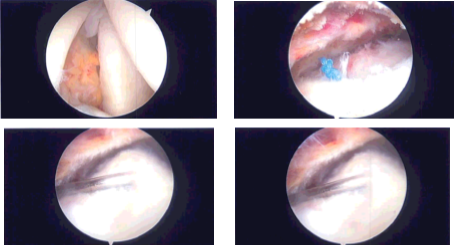

Examination of the joint showed a high- grade partial-thickness rotator cuff tear in the region of the supraspinatus. It also showed intact cartilage as well as labrum. Debridement of the rotator cuff tear was performed from the intra articular region.

The arthroscope was inserted into the subacromial region where debridement of the bursa was performed with the use of shaver. There was acromial spur, which was removed after use of Coblation wand, followed by a bur to remove the spurring. The CA ligament was released with the use of a Coblation wand.

The rotator cuff was found to be high- grade partial in the region of supraspinatus. Decision was made to repair the rotator cuff tear with the use of anchors and sutures. Footprints were developed and decorticated for healing to happen. A Healicoil anchor was inserted into the humeral head.

The tails of the suture were passed sequentially into the rotator cuff tear and tied over each other. A good repair was achieved. There was AC arthritis, which was cleaned with the use of Coblation wand and 1 cm of distal clavicle was excised with the use of a bur. Final pictures were taken and saved.

Intraoperative Arthroscopy Images